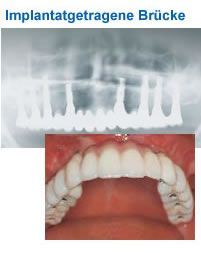

Implantatgetragene Brücke

Festsitzender Zahnersatz ist komfortabel und kommt der Natur am nächsten.